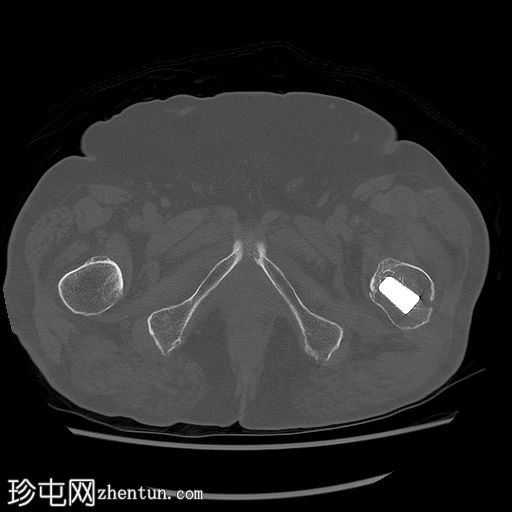

CT扫描

轴向骨窗

左股骨内存在轻微移位的假体周围骨折。

左大腿前部可见大量肌肉,可能提示血肿。但未见明显可引流积液。